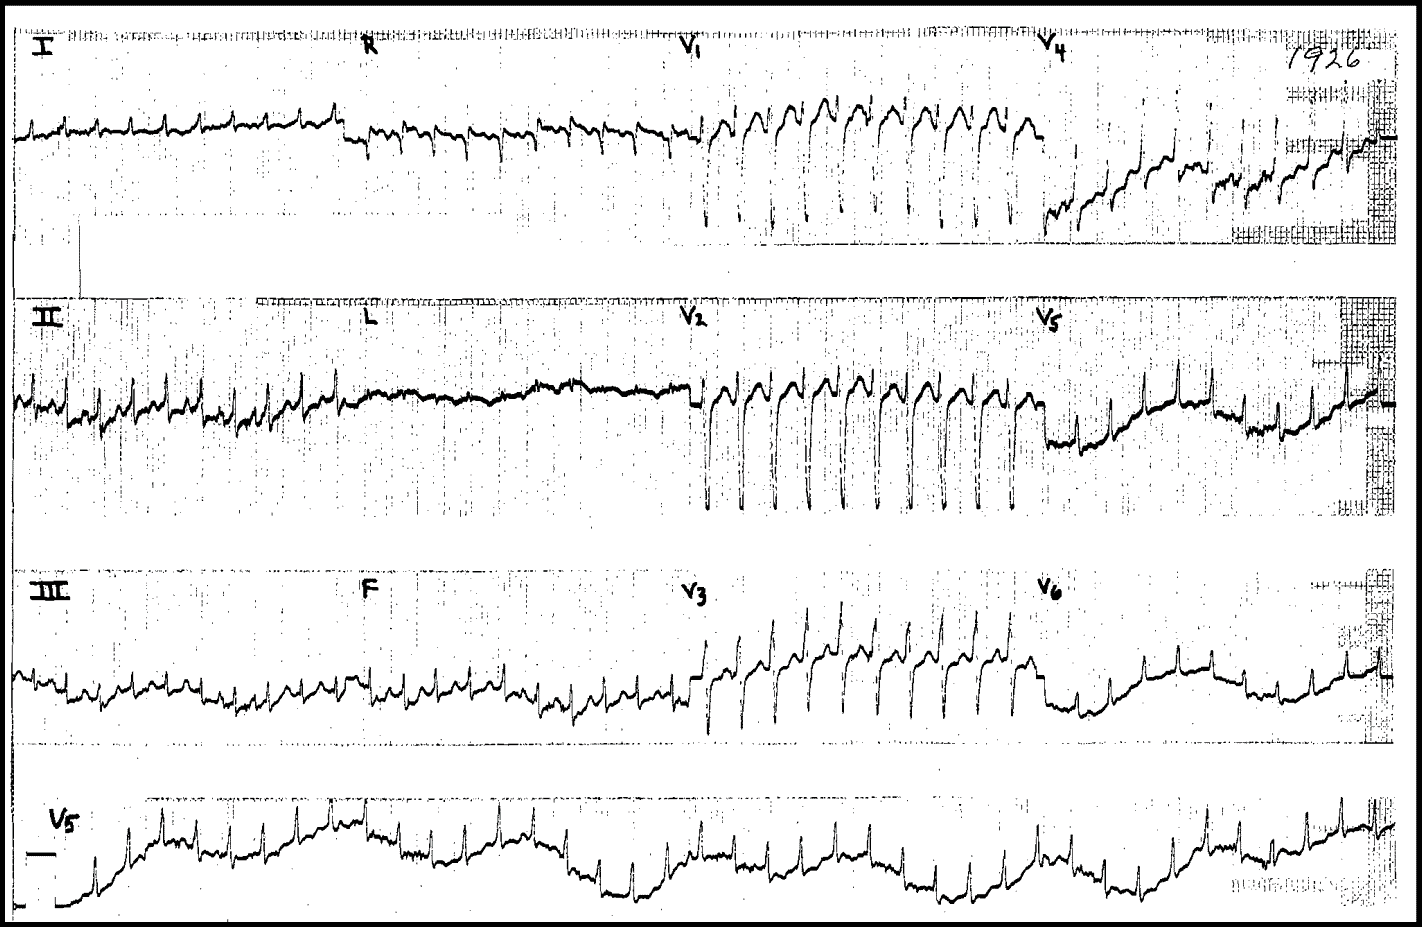

48-year-old man with palpitations and dyspnea.

What’s the rhythm ?